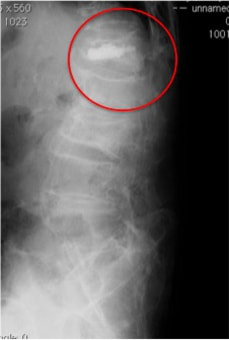

半年程前に耕運機から転落し、第1腰椎圧迫骨折で他院にて3週間入院していました。

術後1週目で抜糸・レントゲン撮影を行い、骨や術創部の状態を確認した上で異常もみられなかったため、予定通り術後8日目での退院となりました。

経皮的椎体形成術により下の写真の様に姿勢の改善が期待できます。